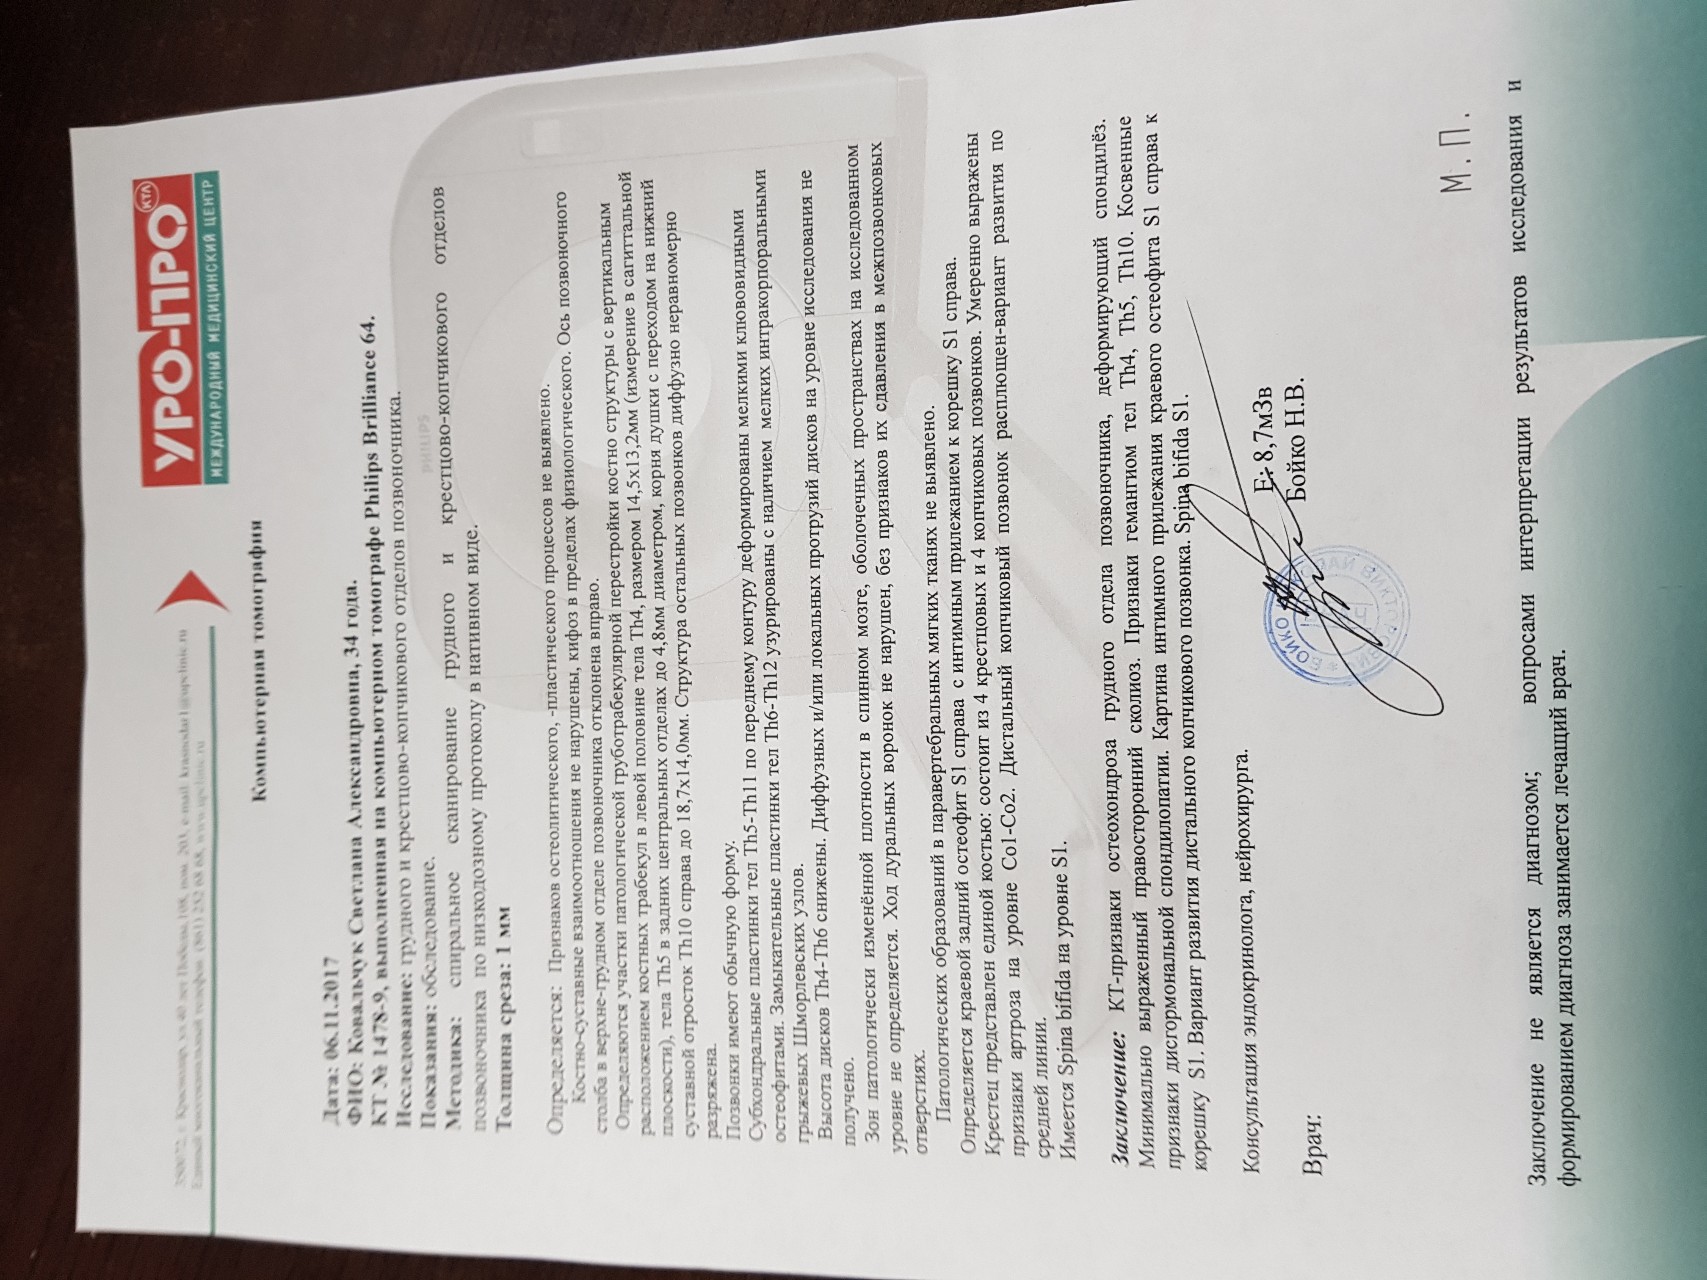

Рентгеновские снимки крестцово-копчикового отдела позвоночника